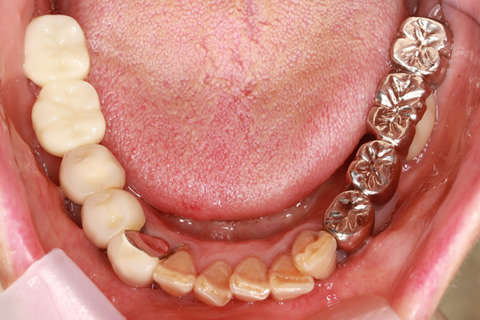

症例2

治療前

インプラント埋入時

治療後

- 年齢・性別

- 57歳男性

- 治療期間

- 3ヶ月

- 抜歯

- なし

- 治療費

- 154万円

- 備考

- 左上5.6.7 及び左下6.7欠損

- 治療内容

- 左上5.6.7と左下6.7欠損部にインプラント埋入

- 施術の副作用(リスク)

- オペによる知覚障害。インプラントによる歯肉炎。インプラント脱落。